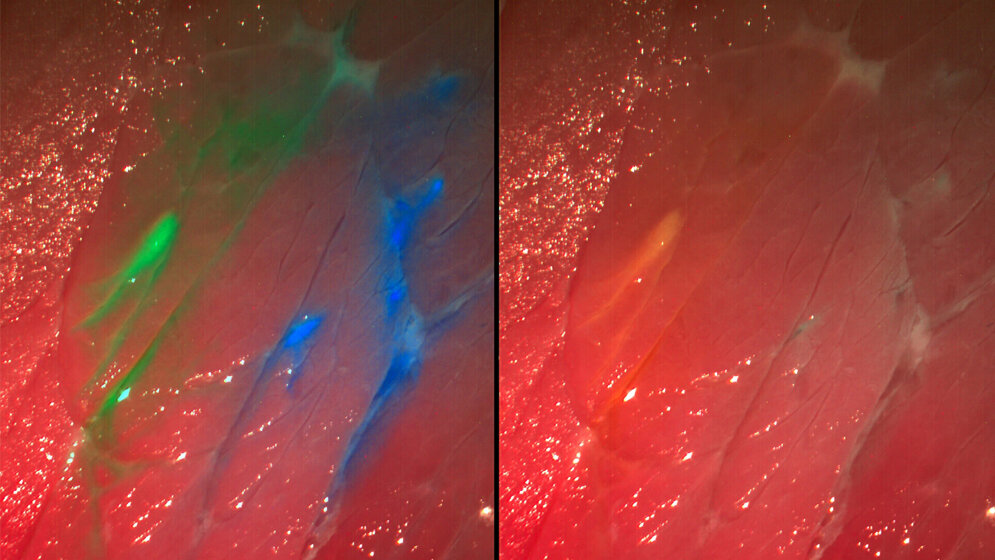

Mit Fluoreszenz ist es schon heute in einigen Bereichen möglich, tumorartiges Gewebe sichtbar zu machen. Dabei wird der Stoff, der die betroffenen Stellen aufleuchten lässt, entweder oral verabreicht oder direkt in die Blase eingeleitet. Hier gibt es aber noch Optimierungspotenzial. So ist der zugeführte Farbstoff viel schwächer als Licht. In der Neurochirurgie muss der Mediziner daher den Raum abdunkeln, um ihn zu sehen. In der Urologie muss er auf das Farbbild des Endoskops verzichten, wenn er die angefärbten Stellen betrachten will.

Das Kamerasystem der IPA-Wissenschaftler, das sie „Multispektrale Intraoperative Echtzeit-Bildgebung“ nennen, zeigt den Farbstoff und das Farbbild gleichzeitig an. Die Kamera, bei der einige Lichtfarben geblockt sind, macht viele Aufnahmen unmittelbar hintereinander. Eine spezielle Software überträgt die Bilder daraufhin in Echtzeit auf einem Monitor im OP, wo sie mit den Farbbildern des Endoskops überlagern. „Da der Mediziner jetzt beide Aufnahmen gleichzeitig sieht, ist es für ihn einfacher, den Tumor zu entfernen“, betont der Wissenschaftler. In Zukunft sei es auch vorstellbar, empfindliche Strukturen wie Nerven, die keinesfalls verletzt werden dürfen, damit farbig hervorheben. (idw, red)